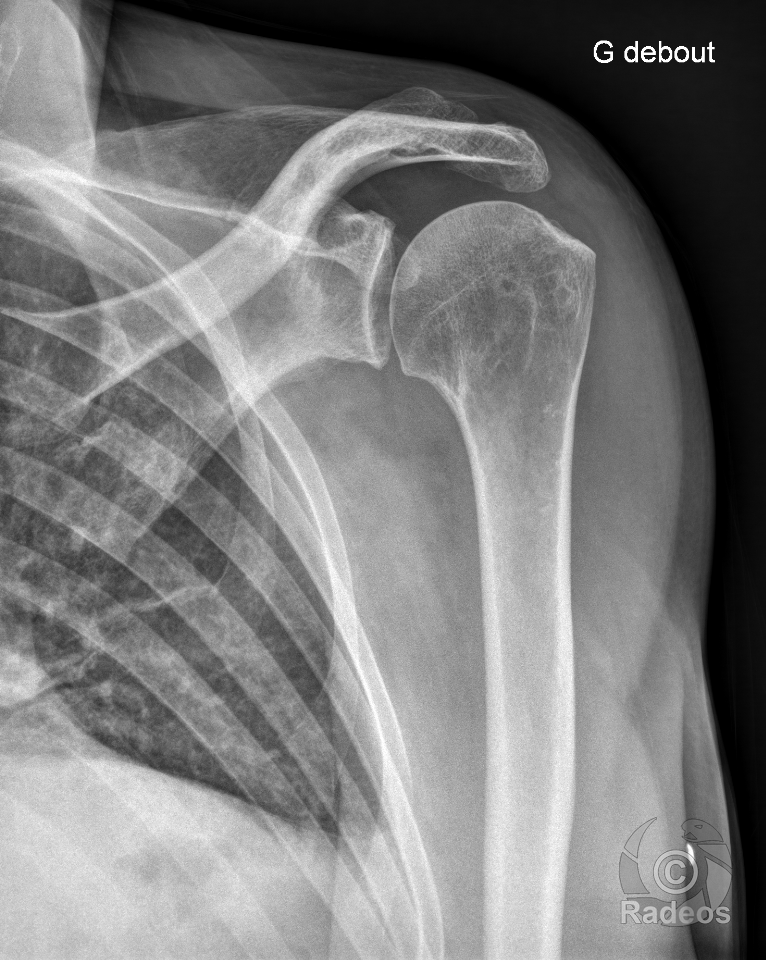

HOT CASE

Trouvez le diagnostic du cas du jour